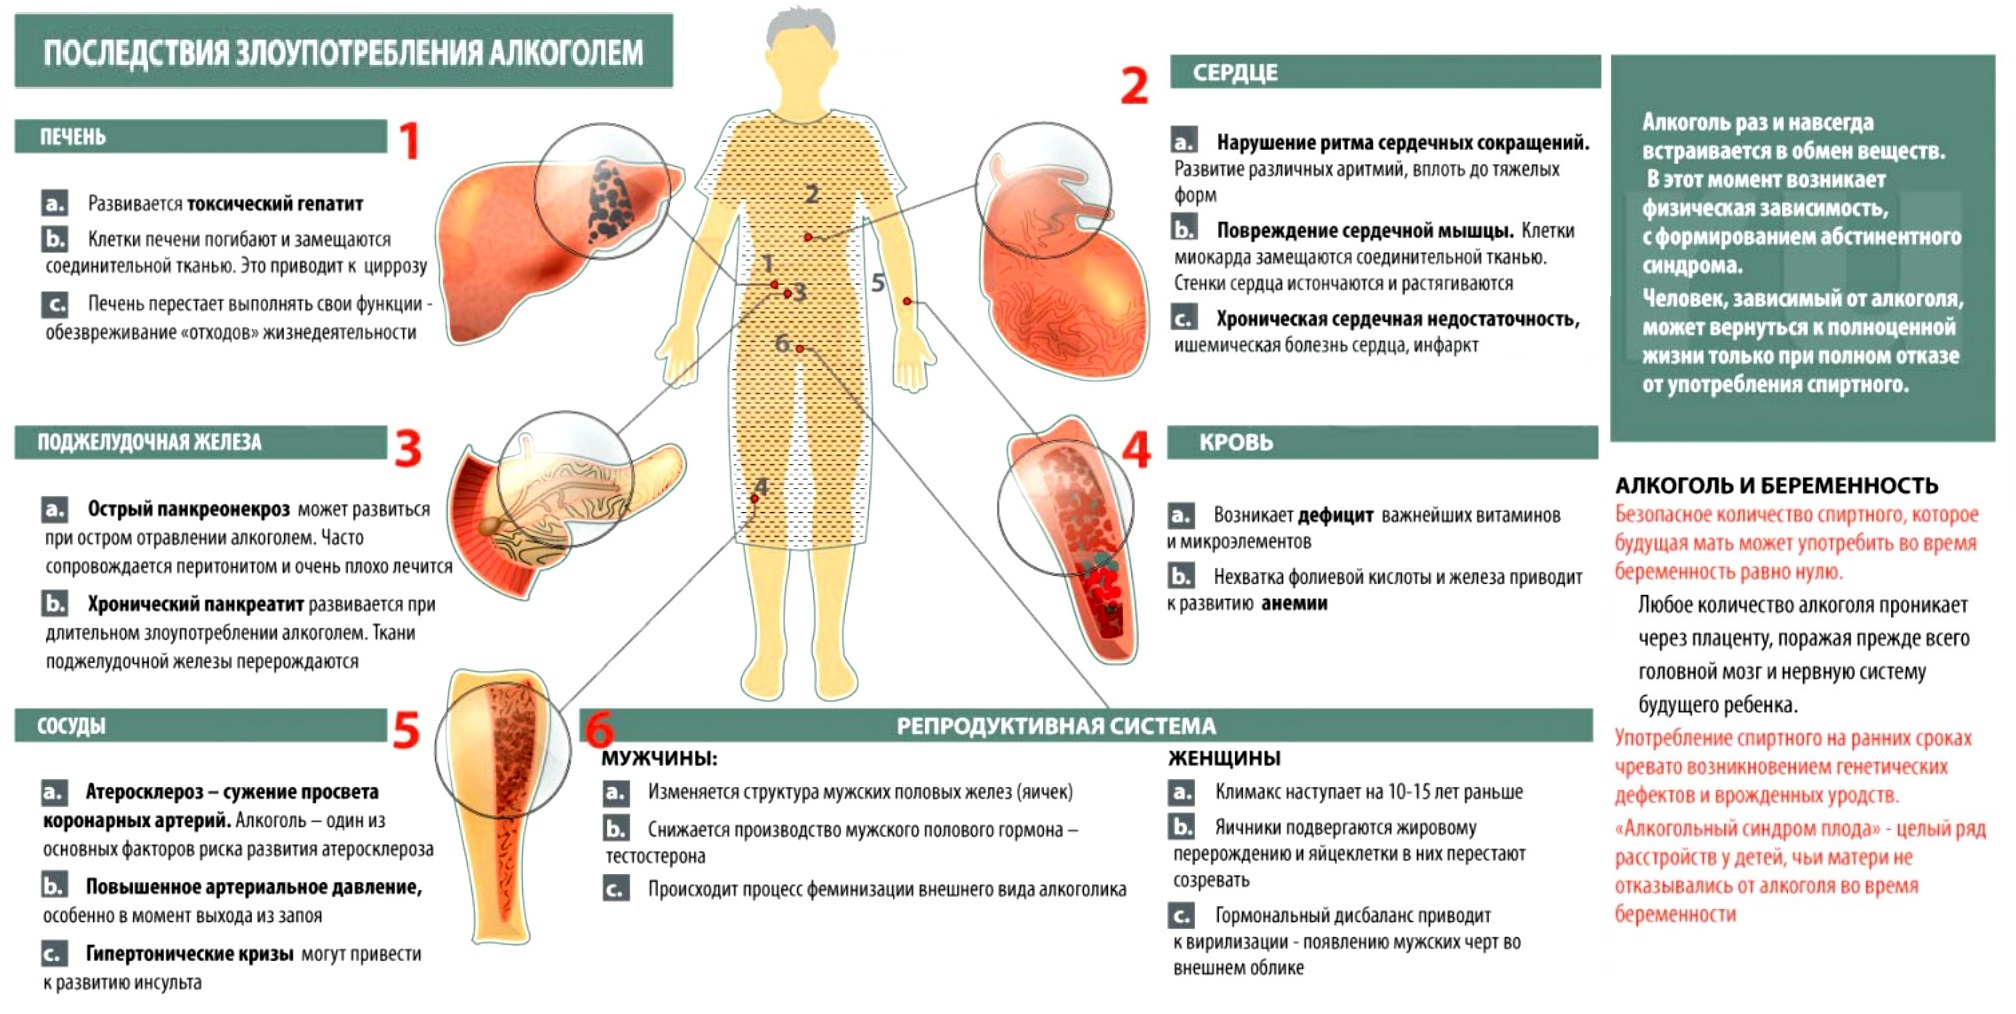

Причинами почечной недостаточности могут быть различные заболевания, травмы или генетические факторы.